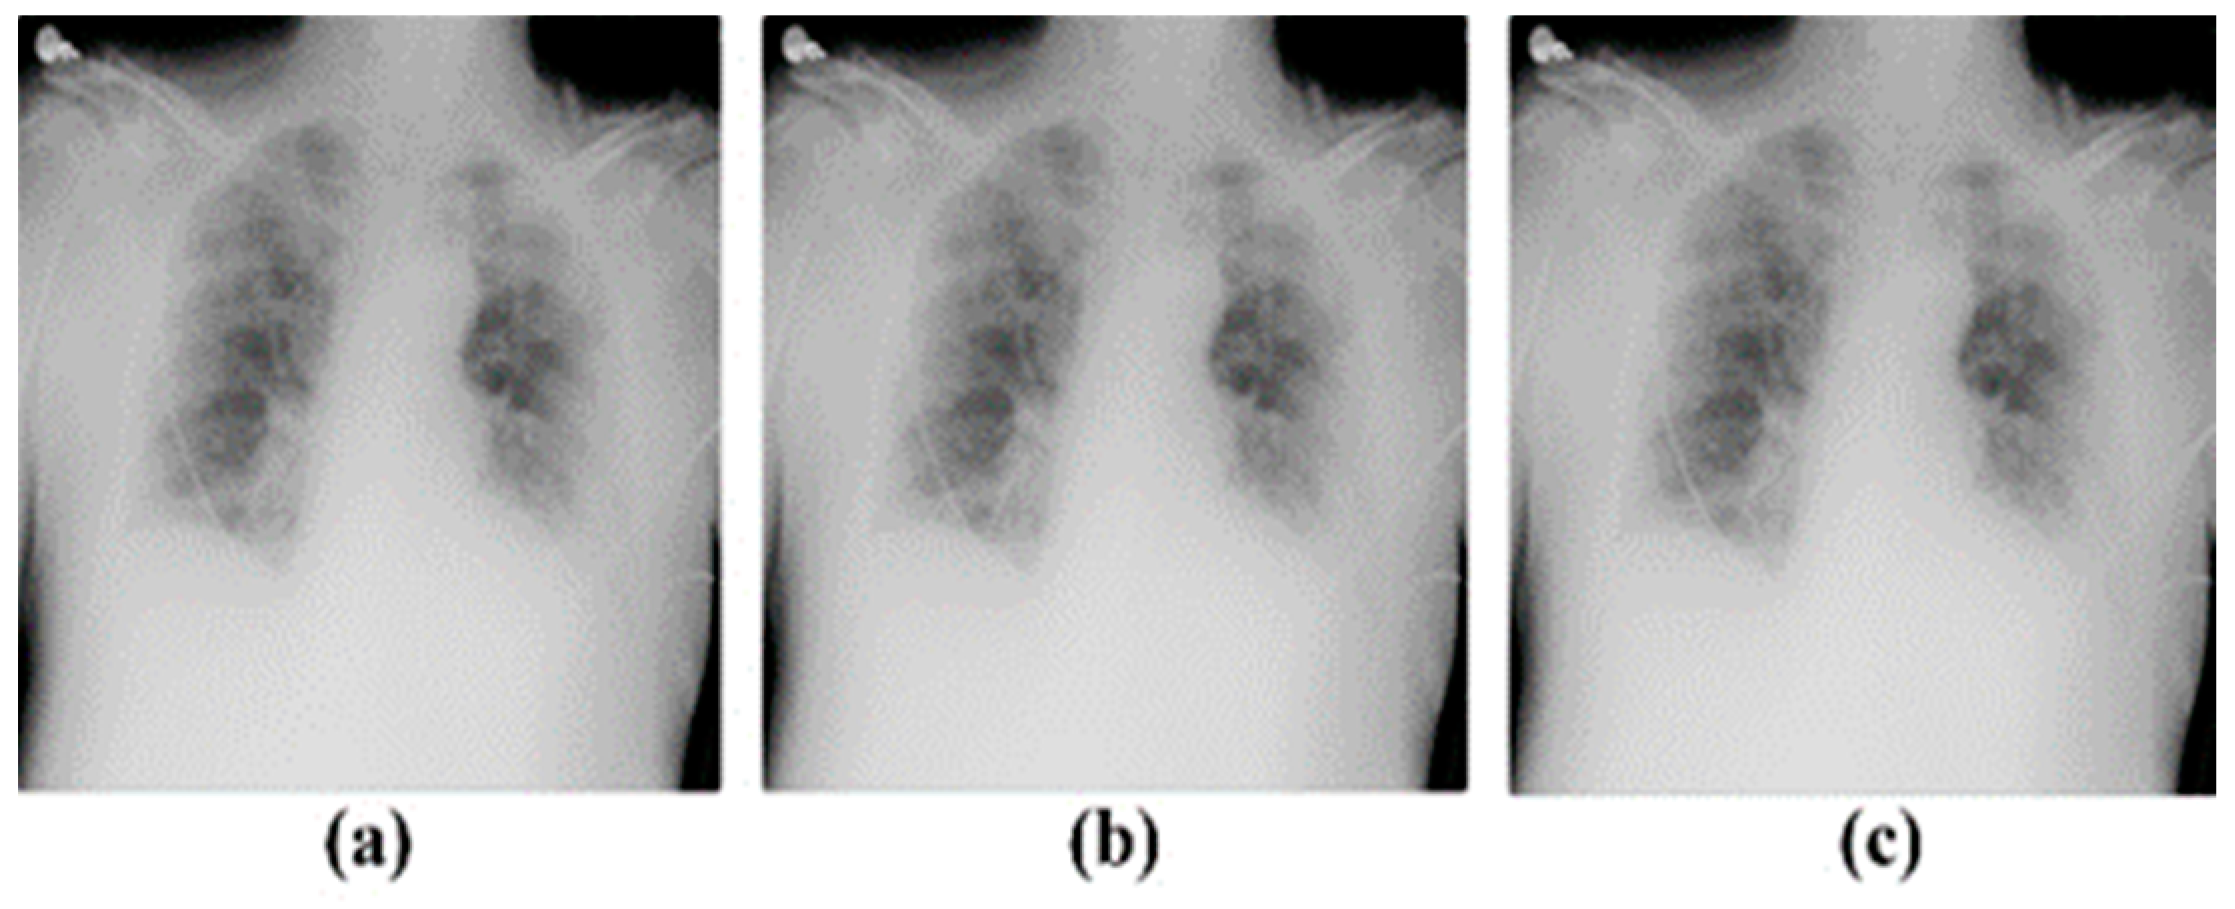

2.2. Pre-Processing

3.2. With the Enhancement Technique